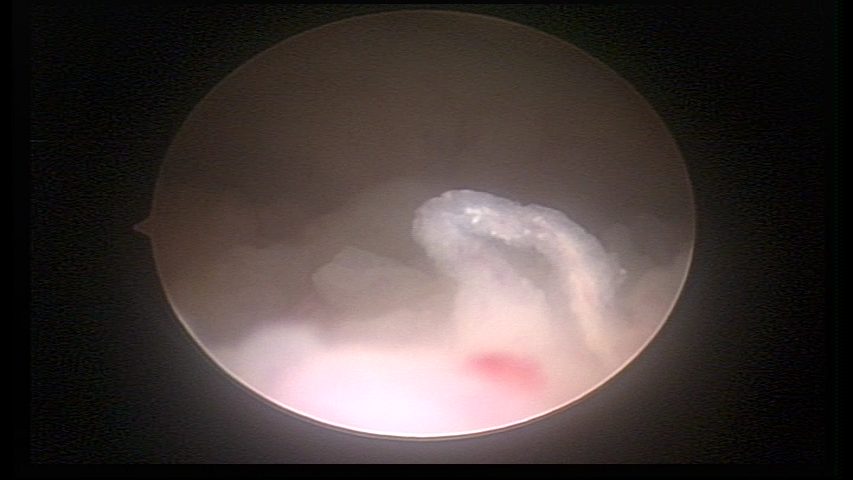

It may present a variable range of macroscopic aspects, with a pseudolopypoid aspect; resembling cerebroid tissue or presenting a decidual reaction; superficial vascularization is more evident presenting vessels in the shape of corkscrew or spirals also viewing the vascularization with atypias, with an increase on the thickness of the superficial vessels, tissue in necrosis and small dendrites (papillomatous) may be found.